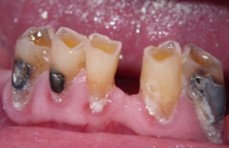

8 local contraindications for bridge work